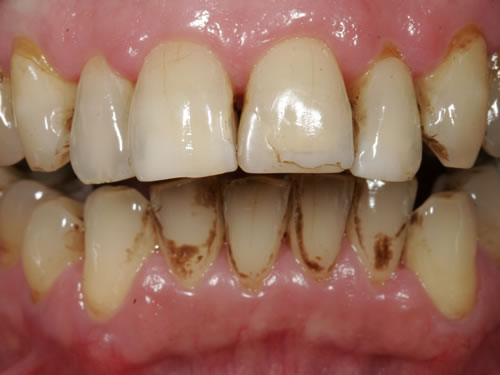

In den meisten Fällen ist nach der Untersuchung und Planung noch eine Vorbehandlung notwendig. Zunächst wird routinemäßig eine professionelle Zahnreinigung durchgeführt, um die Keimzahl in der Mundhöhle und in den Zahnfleischtaschen zu reduzieren (Abb. 5.11, 5.12). Anschließend sollten alle kranken Zähne, entzündetes Zahnfleisch oder auch Kiefergelenkerkrankungen behandelt werden. Die Planung der Einpflanzung sollte immer unter dem Gesichtspunkt der Sanierung des gesamten Gebisses erfolgen. Sie umfasst die Auswahl der geeigneten Implantate, ihre Anzahl und die genaue Position. Diese Vorbereitungen sind sehr wichtig, um nach der Einheilungszeit einen Zahnersatz anfertigen zu können, der die Wiederherstellung der Funktion und der Ästhetik gewährleistet.

Abb. 5.11: Zustand vor professioneller Zahnreinigung.

Abb. 5.12: Recall 1 Woche nach der professionellen Zahnreinigung durch Prophylaxeassistentin.